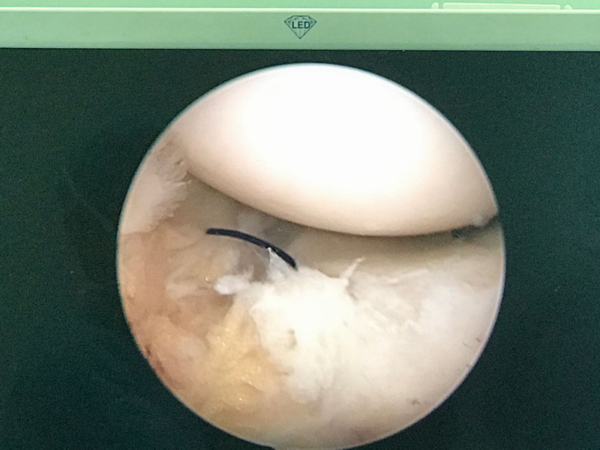

關節鏡下撕裂半月板予以縫合

近日,在四川打工的董先生在一次干活時不小心扭傷膝關節,疼痛難忍,在當地醫院診斷為膝關節半月板損傷,當地建議切開關節手術治療,這讓他很糾結與恐懼。聽說市中醫院可以微創手術,專程從四川趕回臨滄,來市中醫院就醫,經醫院外科骨科組醫師詳細會診,確認手術指針,并向其介紹膝關節鏡手術切口僅5mm,且安全有效,患者欣然接受,在市中醫院做了膝關節鏡下檢查清理+半月板修補手術,術后患者恢復良好、傷口瘢痕小、未出現任何并發癥。

市中醫院外科(骨科組)成功完成膝關節鏡手術,標志著外科(骨科組)在微創領域又一新的發展和突破,同時該技術目前達到市內先進水平。